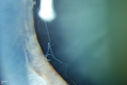

Pseudoexfoliation Material Peeling.386 viewsPatient comes in for regular eye exam. Last exam was 8-years ago. Complains of decrease in VA. VA was 20/30, right eye and 20/40, left eye. Slit lamp photography shows pseudoexfoliation peeling of the lens within 360-degrees. Pseudoexfoliation ring is present centrally. IOP was normal. Will revisit in 3-months for follow up.     (0 votes)